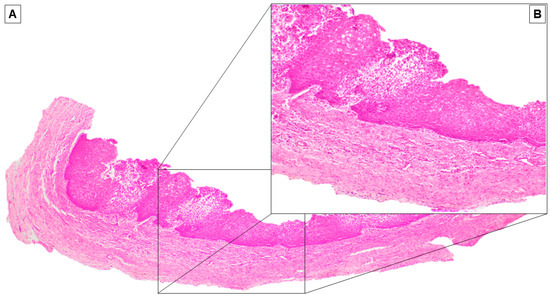

2. Case Report